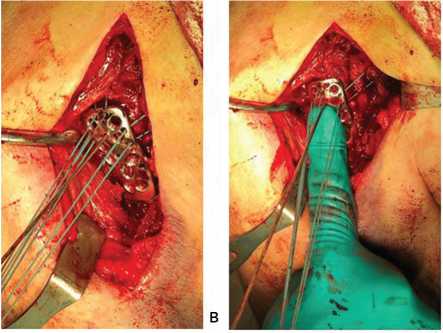

Первым этапом методики было выделение и прошивание сухожилия подлопаточной мышцы нерас-сасывающимися нитями (Терилен 5, FiberWire 2), которые затем фиксировали на держателе (рис. 1). Далее идентифицировали акромиально-клювовидную связку, отводили её кверху и прошивали сухожилие надостной мышцы. Особое внимание уделяли подбору шовного материала, более тонкие и прочные нити позволяли минимизировать размер узлов после фиксации. На заключительном этапе выделяли и прошивали сухожилие подостной мышцы, используя тракцию за ранее прошитое сухожилие надостной мышцы для облегчения доступа.

В результате формировали три нитевых джойстика (подлопаточный, надостный и подостный), которые обеспечивали полноценный контроль положения костных отломков и головки плечевой кости.

На следующем этапе оперативного вмешательства последовательно проводили нити от сухожилий ВМП через специальные отверстия в пластине, предназначенной для остеосинтеза проксимального отдела плечевой кости (рис. 2). Особое значение при этом имеет то обстоятельство, что большинство переломов данной локализации развивается на фоне выраженного остеопороза и дефицита костной возраста со сниженной

Следующей важной манипуляцией было натяжение нитей, фиксирующих элементы ВМП, при одновременном пальцевом прижатии пластины к костным структурам проксимального отдела плечевой кости. Данный технический прием обеспечивал точную и стабильную репозицию костных отломков, плотное прилегание имплантата к костной поверхности (рис. 3).

Рис. 3. Техника репозиции перелома:

а — вид раны после прошивания сухожилия мышц ВМП;

б — продевание нитей через пластину;

в — установка центральной спицы;

г — репозиция на пластине;

д — ЭОП контроль до репозиции, е — репозиция проксимального отдела кости на пластине, контроль ЭОП